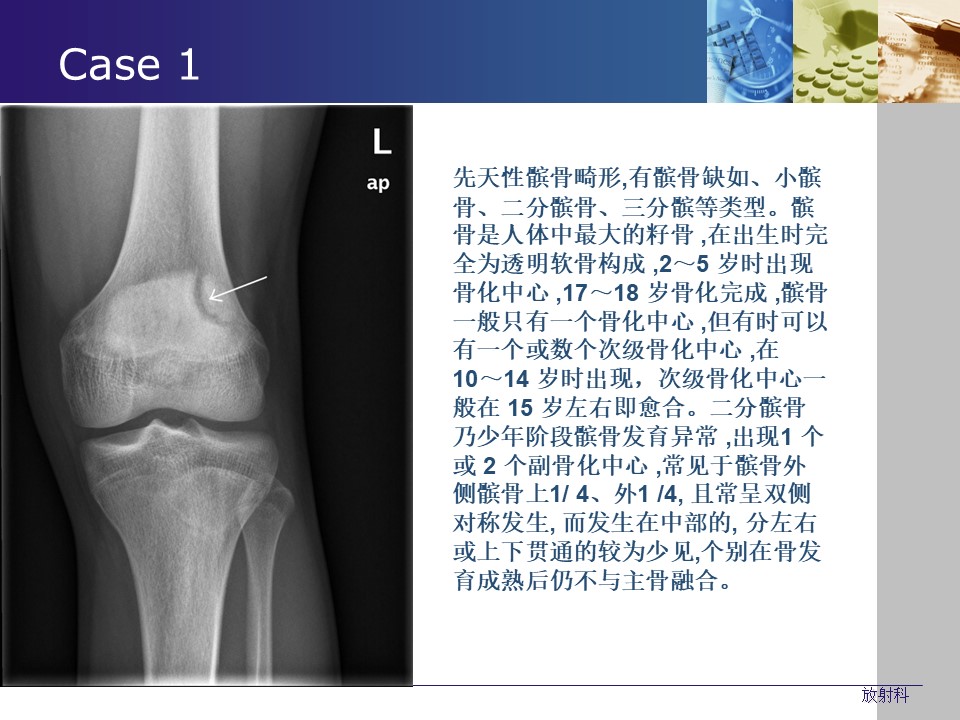

“常见生理(解剖)变异与撕脱骨折的影像学鉴别PPT” 的相关文章